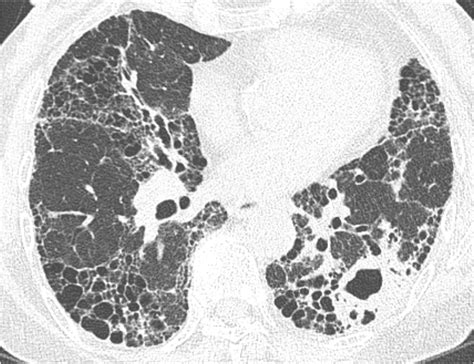

Diagnosing Mac Lung Disease involves a combination of clinical evaluation, laboratory tests, and imaging studies. The diagnostic process typically includes:

• Imaging Studies: Imaging tests like X-rays, CT scans, or MRIs to assess organ involvement and detect any abnormalities.